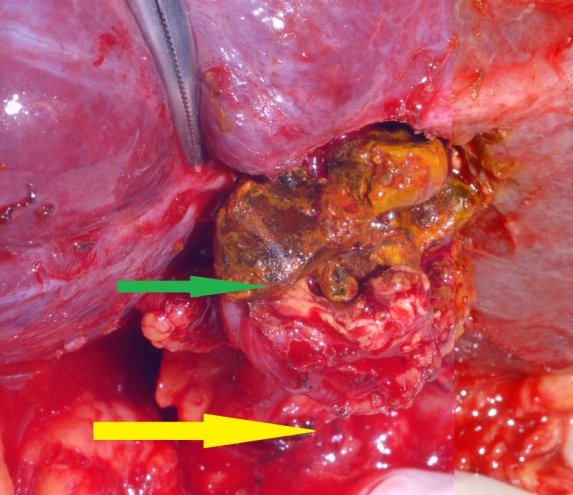

Red arrow — Inflammatory reaction between the hepatic flexure and gallbladder. Green arrow — Gallbladder. Yellow arrow — Right colon (Courtesy Dr. V. Penopoulos)